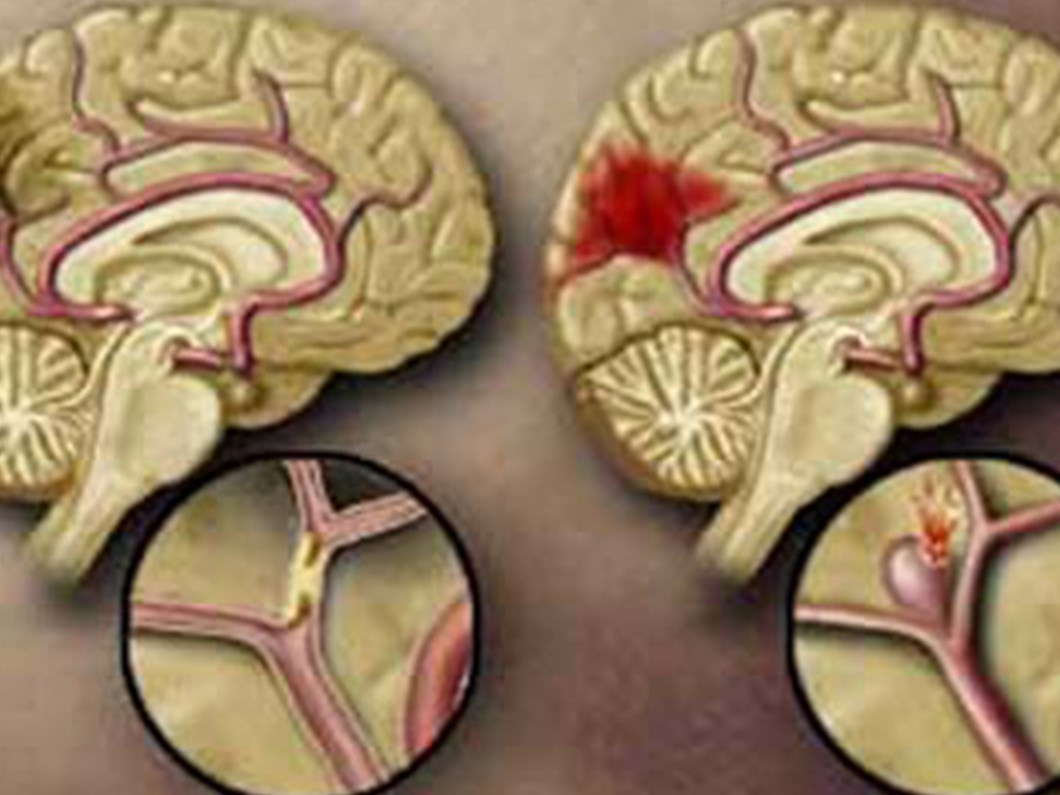

Beyin kanamasında ne olur. Kaza ya da şiddet nedeniyle oluşan travmatik beyin kanamalarında beynin tüm bölgesi etkilenir. Bu semptomlar yüz kol veya bacakta ani karıncalanma halsizlik hissizlik veya felç içerebilir. Beynin kanamadan etkilenen bölgesine göre konuşmada bozukluk kol ve bacakta kasılmalar bilinç kaybı sağ ya da sol tarafta uyuşma veya kuvvet kaybı ya da felç olabilir. Ancak beyin kanamasında devam eden günlük davranışların hislerinde azalma meydana gelir.

Bu yazımızda beyin kanaması öncesindeki belirtilerin neler olduğunu beyin kanamasının. Beyin kanaması tam teşhisi için bilgisayarlı beyin tomografisi çekilir kan olgusuna oldukça hassas olan bu yöntem kanın nerede toplandığını tespit etmekte yardımcı olur. Travma dışı nedenlerle oluşan beyin kanamaları kanamanın şiddetine bağlı olarak baş ve veya ense ağrısından ani bilinç kaybına kadar çeşitli. Kanamanın beyin kabuğu ile beyin dokuları arasında oluşanına ise subaraknoid beyin kanaması ismi verilir.

Spontan beyin kanamaları ise genel olarak beyin ile beyin zarı arasında ya da beyin içinde meydana gelir. Beyin kanaması sonrası hayatınıza normal olarak devam etmeniz biraz güç olacaktır.